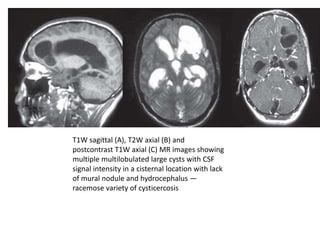

T1W sagittal (A), T2W axial (B) and

postcontrast T1W axial (C) MR images showing

multiple multilobulated large cysts with CSF

signal intensity in a cisternal location with lack

of mural nodule and hydrocephalus —

racemose variety of cysticercosis